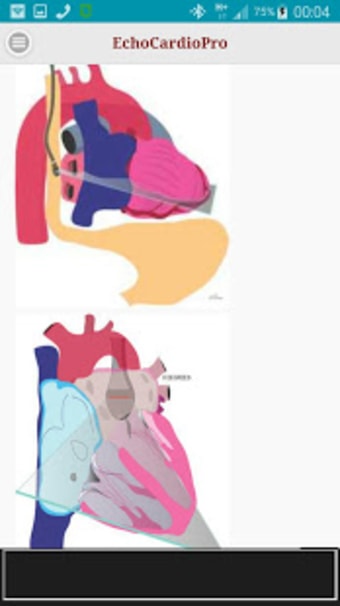

Aplikacja dostarcza kompleksowych informacji na temat echokardiografii przezklatkowej (TTE) i echokardiografii przełykowej (TEE) oraz ich odpowiednich korzyści w ocenie czynności skurczowej i rozkurczowej lewej i prawej komory, regionalnego ruchu ściany, wad zastawkowych serca i chorób osierdzia. Zawiera również szczegółowe informacje na temat różnych widoków, takich jak długoosiowy przysercowy, krótkoosiowy przysercowy, wierzchołkowy, podżebrowy, nadobojczykowy, śródprzełykowy, poprzezżołądkowy, głęboko poprzezżołądkowy i wysoko przełykowy.